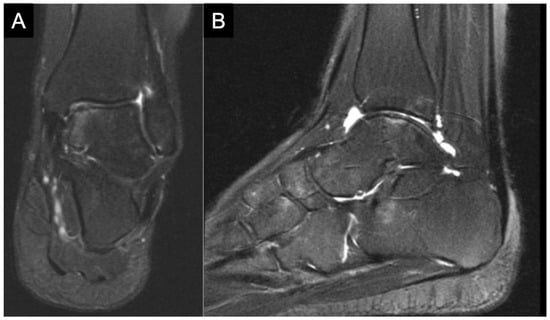

2. Etiology and Epidemiology

3. Diagnostics